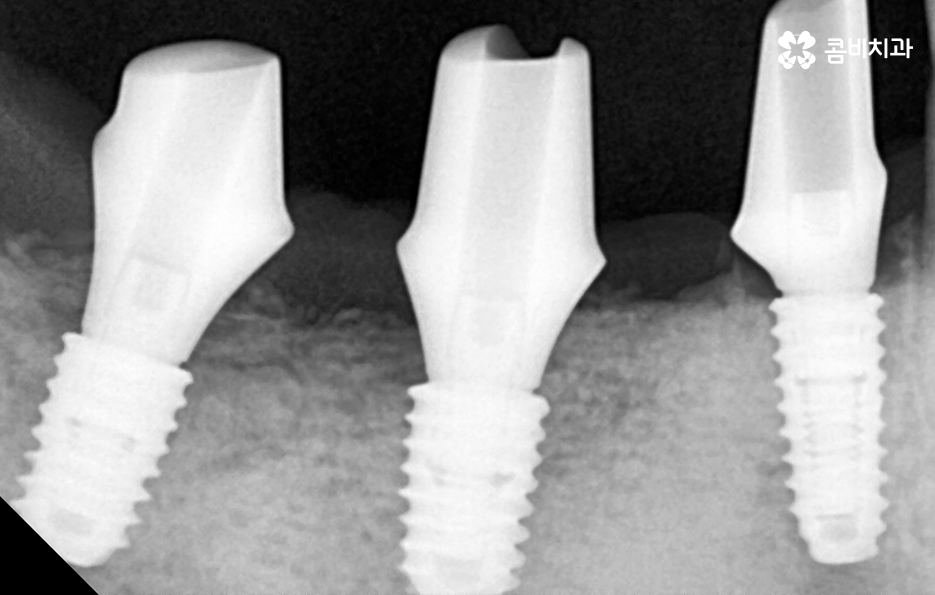

위 환자분의 케이스는 치주염이 심해져서 치아를 잃게 되기도 했지만 윗니의 경우 브릿지로 치아 기능을 유지하다가 결국 임플란트를 하게 된 사례로 볼 수 있어요

과거에는 임플란트 치료 자체가 없어서 브릿지나 틀니와 같은 치료를 할 수 밖에 없었지만 브릿지와 틀니의 한계점은 치아의 기능적인 부분에서도 한계점이 분명하지만 그에 더해 치조골이 점점 내려 앉고 흡수된다는 점에서도 임플란트의 장점이 명확하다고 할 거예요